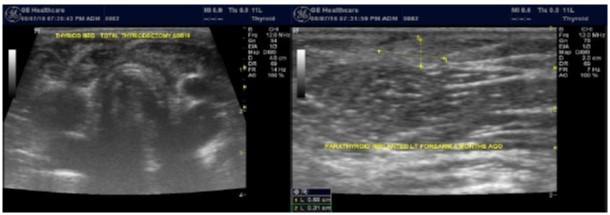

Any nodule with intermediate indeterminate cytology or higher on FNA should go to surgery 23. Among our patients population, one patient with nodular pathology and tertiary hyperparathyroidism was found to have papillary carcinoma of the thyroid during parathyroiectomy. Total thyroidecotmy was done and the patient got forearm implantation of one of the parathyroid glands, Figure 6.

Figure 6.Total thyroidecotmy and forearm implantation of the parathyroid gland

Total thyroidecotmy and forearm implantation of the parathyroid gland

Some experts prefer partial or total thyroidectomy if the cancer is already confirmed before

surgery. However, no consensus exists about partial thyroidectomy 23. Some authors recommend ablation using radioactive iodine (I-131) for high-risk patients with postoperative thyroid replacement therapy but the benefits of administration remain controversial in low-risk patients 23, ,24. Follow up with regular TSH is recommended following complete resection of thyroid cancer. The TSH concentration should be in the target range of 0.5 μU per mL. Greater suppression may be necessary for high-risk patients and those with a metastatic or locally invasive tumor.